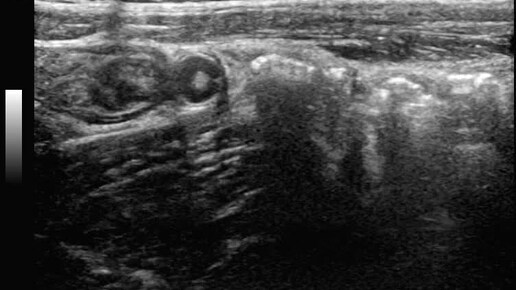

Ультразвуковые находки от врача УЗД Зорина Я.П.